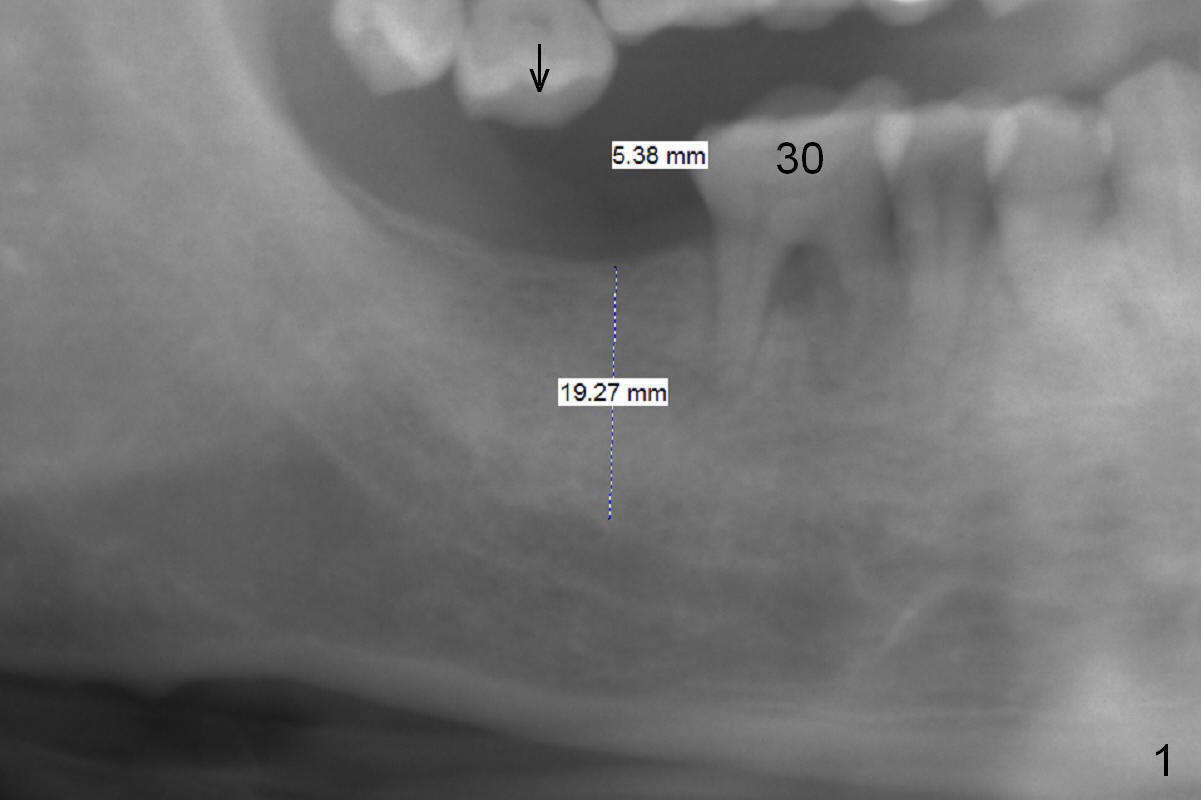

A 59-year-old man will return for #31 implant placement following #13 and 15 ones.  Since the bone density in the original socket seems to be low, start osteotomy with 1.2 mm drill (flapless), followed by DIO bone expanders as deep as possible.  When initial intraop PA is taken, measure the thickness of the gingiva.  Since the implants on the left side were placed recently and the tooth #2 is supraerupted (arrow), achieving high stability at #31 is priority.  A long implant is an easy choice.  Prepare 18 mm drills.  Take BW to confirm that the implant is placed subcrestally, if necessary.  A healing abutment is most likely placed to reduce postop micro-movement.